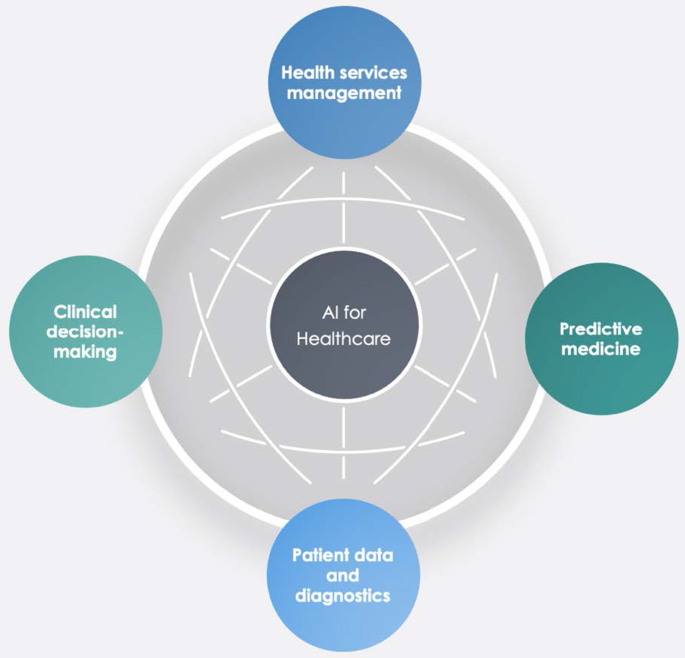

The investigation showed that the literature in this field is emerging. It focuses on health services management, predictive medicine, patient data and diagnostics, and clinical decision-making. The United States, China, and the United Kingdom contributed the highest number of studies. Keyword analysis revealed that AI can support physicians in making a diagnosis, predicting the spread of diseases and customising treatment paths.

A topic dendrogram study that identifies five research clusters: health services management, predictive medicine, patient data, diagnostics, and finally, clinical decision-making.

An in-depth discussion that develops theoretical and practical implications for future studies.